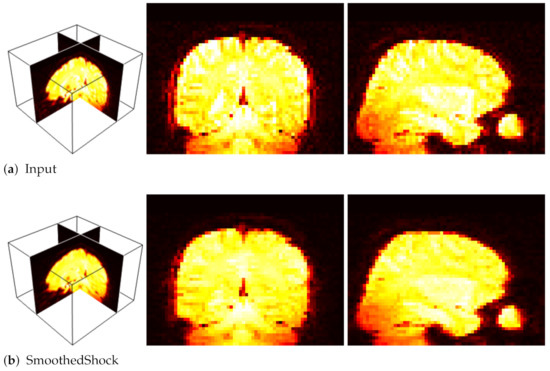

4.1. Image Segmentation